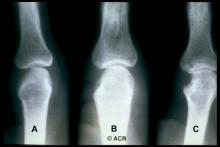

Management of arthralgias before a certified rheumatoid arthritis (RA) diagnosis is challenging - should one use DMARD therapy before clinically evident synovitis in a preemptive effort to avoid or forestall the diagnosis or damage of RA? A novel study has shown that MTX initiated in subclinical, pre-diagnosed, arthralgia patients did not prevent the development of inflammatory arthritis, but did appear to modify the disease course (compared to placebo), as shown by serial MRI.